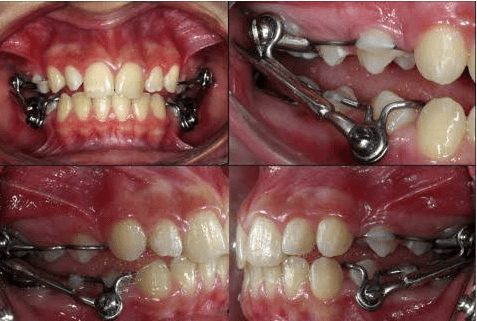

Fixed Functional Appliances

Specialized orthodontic devices used to correct jaw discrepancies in growing patients. These appliances help guide jaw growth and improve the relationship between upper and lower jaws.

Non-Removable Design